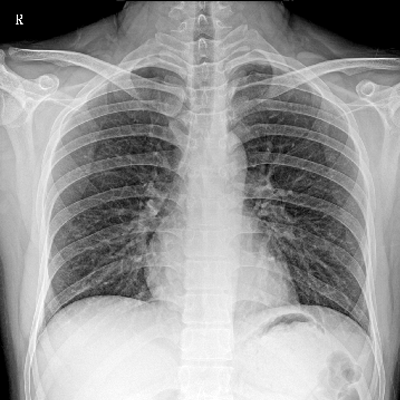

輕量化設(shè)計(jì) 小巧靈活 PLX5100

用于影像科、急診室、病房、ICU、手術(shù)室等多場景應(yīng)用。

● 數(shù)字化無線平板成像,操作簡便,成像質(zhì)量高